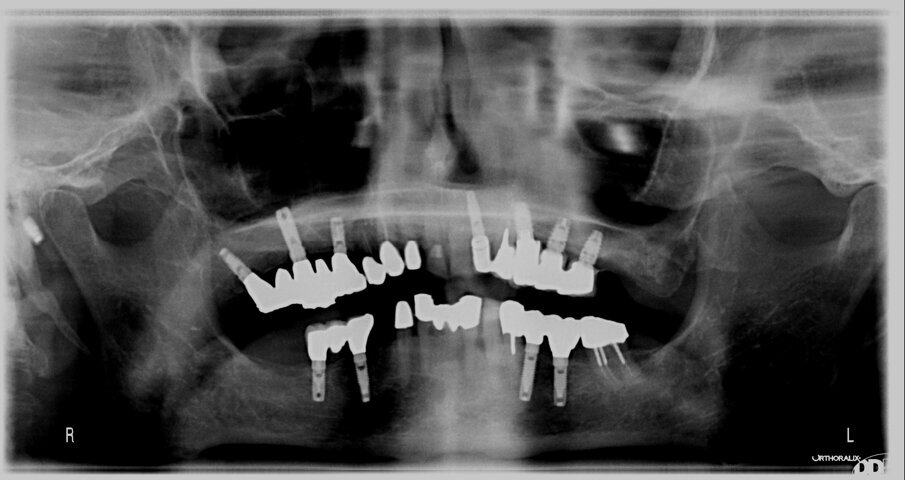

Sono stati inseriti un totale di 50 impianti di cui 25 TBR “Connect” Z1 e 25 M 3.2 Z1 nelle regioni estetiche da 1.4 a 2.4 e altrettanti 25 impianti nelle regioni estetiche comprese tra 3.4 e 4.4, per un numero totale di 50 impianti Z1.

Il 75% degli impianti sono stati collocati con tecnica post-estrattiva e carico differito a 75 giorni dall’inserimento, il restante 25% ugualmente con tecnica post-estrattiva a carico immediato entro le 72 ore dall’intervento. Gli impianti sono stati inseriti con torque di avvitamento pari a 45 N/cm2 e con una profondità di inserimento del collare in zirconia di circa 1 mm sotto la cresta ossea. Nel caso degli impianti a carico differito è stata impiegata la vite di guarigione post chirurgica per il mantenimento di un giusto gap connettivale e tecnica di sutura a materassaio orizzontale con ancoraggio periosteo per stabilizzare il coagulo nello spazio compreso fra impianto e corticale alveolare.

I casi trattati hanno tutti un follow-up di 3 anni dal carico masticatorio con controlli periodici mensili nei casi trattati con carico immediato e trimestrali per quelli a carico differito. La valutazione del trofismo connettivale è stata eseguita secondo semplici parametri estetici e attraverso l’indice di sanguinamento provocato, che evidenzia un attacco delle fibre circolari (Bianchi et al., 2004). La crescita progressiva di gengiva cheratinizzata e la sua stabilizzazione sono state misurate mediante sondaggio con sonda micro millimetrata e relativa documentazione fotografica nel tempo.

Le foto esplicative si riferiscono a un caso di riabilitazione estetica su paziente maschio di anni 76 con storia di bruxismo, in cui è stato inserito con carico immediato un impianto post estrattivo su 2.2 con mantenimento parziale del tavolato vestibolare nel rispetto del concetto di tunnel protesico di inserzione (Fig. 1). Il collare in zirconia è stato inserito per 1 mm sotto il tavolato e la porzione emergente ha la funzione di mantenimento a balcone del bombè connettivale e quindi di sostegno per i tessuti molli (Figg. 2, 3). La protesizzazione, avvenuta nelle 72 ore successive all’inserimento della fixture, è stata effettuata con impronta pick up e tecnica cementata con corona in PMMA eseguita al cad cam; l’angolo incisale della corona risultava assai smusso distalmente per agevolare i movimenti di svincolo in lateralità poiché il paziente è bruxista, come si evince dalle faccette di usura degli elementi naturali adiacenti (Fig. 4). Nonostante il biotipo gengivale sottile già nelle prime fasi dal carico si può notare l’effetto biomimetico del collare in zirconia e l’accettazione paraimplantare sul versante estetico.